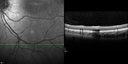

This pleasant 8-year-old child was seen in the office on March 8, 2012. He was examined for glasses and dilated examination showed retinal abnormalities.

VISUAL ACUITY: OD 20/40, OS 20/50. IOP: 12 OU. His lenses are clear.

OD: Vertical C/D ratio is 0.2. There are foveal cysts. There is also a retinal elevation inferiorly and there are patchy peripheral retinal hemorrhages.

OS: Vertical C/D ratio is 0.2. There are foveal cysts. There is peripheral retinal issues with some hemorrhage in some areas of peripheral retinoschisis.

SPECTRALIS-SD-OCT SCAN: The OCT scan does show foveal retinoschisis in both eyes. The average thickness of the macula in the right eye being 420 microns and the cysts appear to be forming predominately in the inner nuclear and inner plexiform layer. In the left eye the OCT scan shows an average central foveal thickness of 414 microns and the cysts in that eye are forming mostly in the inner plexiform inner nuclear layer. The peripheral line scans also show peripheral retinoschisis in both eyes outside the macula. It is a little bit closer in the right eye where the hemorrhage is and you can see vitreoretinal traction at the edge of the schisis cavity. (NOTE: Retinal thickness measured with Spectralis OCT is approximately 70 μm greater than that measured with Stratus OCT. This increased measurement corresponds to the inclusion of the outer segment-RPE-Bruch's membrane complex by Spectralis OCT.)